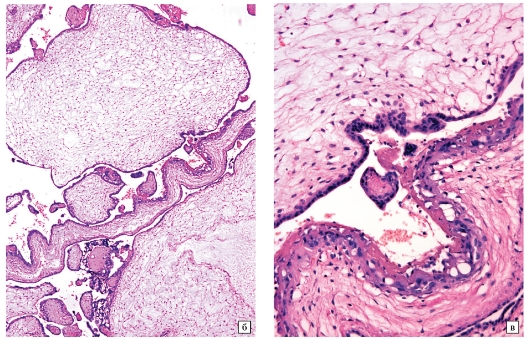

Часть последа с кистозной трансформацией микроскопически представлена крупными отечными ворсинами, в большинстве из которых определяются полости (цистерны), в некоторых ворсинах спавшиеся, и небольшим числом ворсин среднего диаметра с отечной стромой без образования полостей. Сосуды в ворсинах отсутствуют. Выражена пролиферация трофобласта местами с образованием криброзных и сосочковых структур, а также умеренным полиморфизмом клеток (рис. 3, а, б). Встречаются группы некротизированных ворсин, преимущественно располагающиеся вблизи тромбов (см. рис. 3, в). ИГХ-реакция с р57 в трофобласте и строме ворсин отрицательная, во вневорсинчатом трофобласте положительная (см. рис. 3, д, е). Реакция с Ki-67 позитивная в большинстве клеток цитотрофобласта ворсин и во вневорсинчатом трофобласте (см. рис. 3, г).

Рис. 3. Полный пузырный занос. а, б — крупные отечные ворсины с цистернами, некоторые ворсины спавшиеся, выражена пролиферация трофобласта; в — группы некротизированных ворсин; г — многочисленные Ki-67-позитивные клетки цитотрофобласта ворсин и вневорсинчатого трофобласта; д — отсутствие экспрессии р57 в трофобласте и строме ворсин; е — положительная экспрессия р57 во вневорсинчатом трофобласте при отсутствии экспрессии в ворсинах;. а—в — окраска гематоксилином и эозином; г—е — иммуногистохимическая реакция.